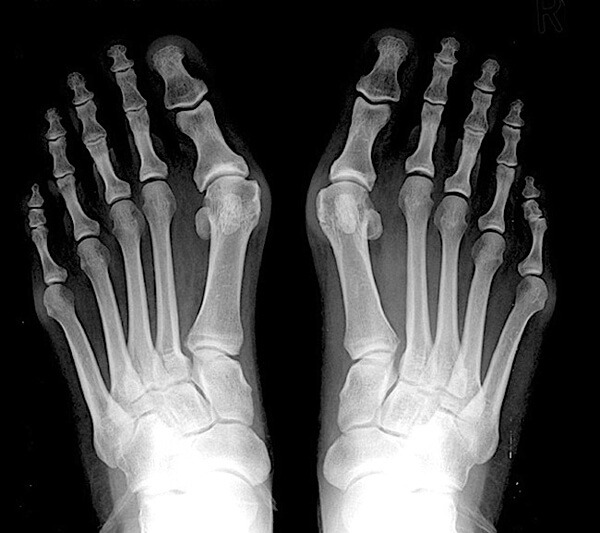

하이힐을 즐겨 신는 여성들의 발을 보면 엄지발가락과 새끼발가락이 서로 안쪽으로 휘어져 있는 것을 볼 수 있다. 좀 더 정확히 얘기하자면 엄지발가락의 제1중족 발가락 관절을 기준으로 발가락 쪽의 뼈가 바깥쪽으로 치우치고, 발뒤꿈치 쪽의 뼈는 반대로 안쪽으로 치우치는 발 변형을 말하는데, 이를 무지외반증이라고 한다.

무지외반증은 앞서 설명한 것처럼 엄지발가락의 제1중족 발가락 관절을 기준으로 발가락 쪽의 뼈가 바깥쪽으로 치우치고, 발뒤꿈치 쪽의 뼈는 반대로 안쪽으로 치우치는 발 변형이다. 이 변형은 발의 수평면에서의 변형을 의미하는 용어이지만 실제로는 발가락이 발등 쪽으로 휘거나 회전하는 변형을 동반한 삼차원적인 변형이다.

일단 무지외반증이 있는 발은 외형적 변형만으로 진단할 수 있다. 하지만 적절한 진단과 치료를 위해서는 의사의 진단이 필요하며(통증이 심한 경우에는 필수) 정도에 따라서는 진찰뿐만 아니라 방사선 촬영 검사가 필요하기도 하다.

위에서 설명했듯이 의사의 진찰과 방사선 소견으로 검사 방법을 나눌 수 있다. 먼저 의사의 진찰을 통한 검사 방법으로는 안쪽 돌출 정도, 관절 자체의 통증 여부, 두 번째 또는 세 번째 발가락 아래의 굳은살 및 통증 여부, 관절 탈구 여부, 새끼발가락 쪽의 돌출 여부 등에 대해 진찰하고, 방사선 소견은 일반적으로 발에 체중이 실린 상태에서 단순 방사선 사진을 촬영해 변형된 각을 측정하고 관절의 퇴행성 변화 여부를 관찰한다.